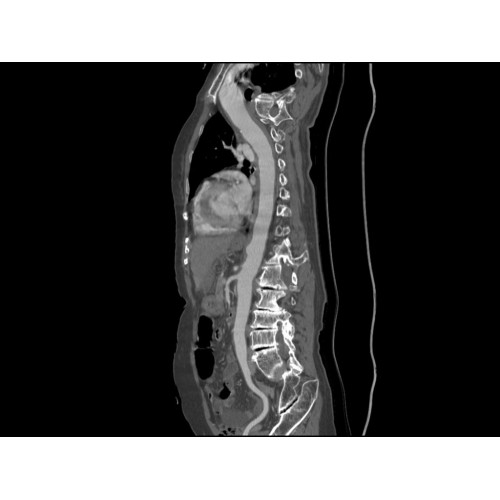

Компьютерный томограф GE Brivo CT385 представляет собой современное диагностическое оборудование, сочетающее высокую точность исследований с повышенным комфортом для пациентов. Этот аппарат открывает новые возможности для детальной визуализации анатомических структур.

Позволяет проводить комплексные исследования всех анатомических зон, включая нейровизуализацию, ангиографию, исследования органов грудной и брюшной полости. Особенно эффективен для раннего выявления онкологических заболеваний.

Специализированные исследования

Обеспечивает высокую точность при кардиологических исследованиях, визуализации костных структур и суставов. Подходит для динамического наблюдения в ходе лечения.